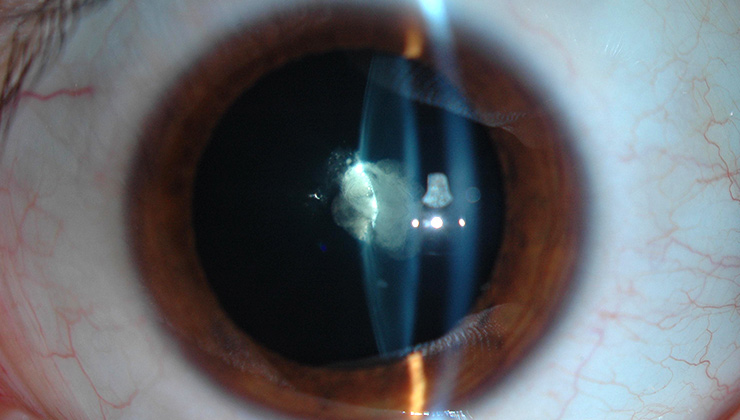

Відповідно до даних нового дослідження, у дітей із двосторнньою катарактою значно частіше виявляли її спадкові та системні причини, аніж у дітей із односторонньою катарактою.

Дослідники провели огляд медичних записів 727 пацієнтів, які пройшли хірургію катаракти у центрах надання медичної допомоги третинного рівня у віці меншому за 21 рік протягом останніх 25 років. Пацієнтів було розподілено на групи за наявністю одно- чи двосторонньої катаракти, а потім вони були диференційовані за зв’язками системних захворювань та очних проявів.

Причина катаракти були виявлена у 66% пацієнтів із двосторонньою катарактою і у 55% пацієнтів із групи односторонньої катаракти. Спадкові причини (21.8%), синдромальні/генетичні/метаболічні причини (23.8%) та лікування онкологічних захворювань або ж тривалий прийом кортикостероїдів (14.7%) спричинили катаракту у більшості із 408 пацієнтів двосторонньої групи. Дисморфологія ока спричинила більшість випадків (48.9%) у 319 дітей з односторонньою катарактою.

У випадках білатеральної катаракти найбільш поширеними системними причинами були: синдром Дауна (5.6%), синдром Лоу (1.7%) та синдром Марфана (4.2%). А найбільш поширеними випадками, що спричинили односторонню катаракту були: очна травма (20%), стійка васкуляризація плода (19.5%) та аномалії сітківки і зорового нерва (5.3%).